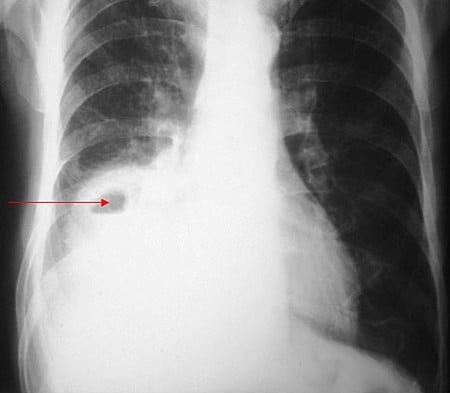

zapalenie płuc - mp.pl

Fot. mp.pl

Ta bakteria w tej chwili nam się częściej pokazuje na co dzień. To jest bakteria, która wywołuje między innymi ciężkie zapalenia płuc i diagnozując zapalenia płuc, my widzimy, że tej mykoplazmy jest więcej, niż było kiedyś. Są też cięższe przypadki. Część dzieci trafia do szpitala. Wymagają cięższego leczenia